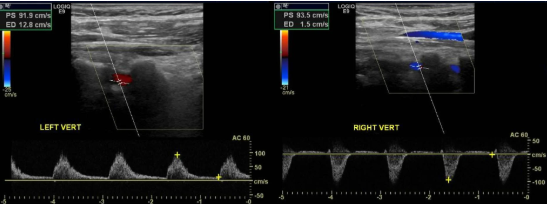

You obtain these images of vertebral arteries.

1. What is this finding right side?

2. What does this indicate?

3. Where is obstruction?

4. Vertebral artery feeds which portion of brain?

5. The two vertebral arteries unite to form?

retrograde flow

subclavian steal

Right subclavian artery that’s proximal to the origin of the vertebral artery

posterior portion

Basilar artery